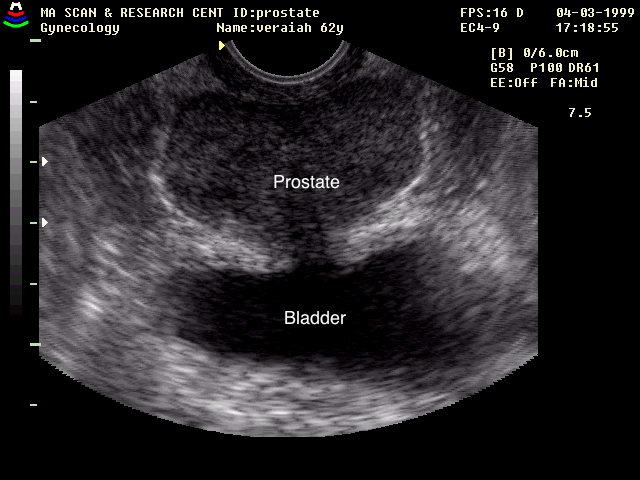

Transrectal

In a transrectal examination, the bladder is below the prostate (the transducer is now closer to the prostate than it is to the bladder)

Source: RadiologyWorld